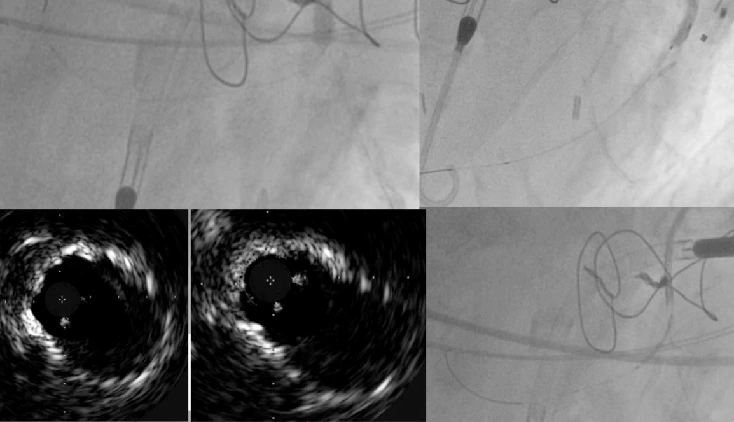

Spezifische klinische Vignetten für geschützte perkutane Koronarinterventionen mit hohem Risiko

In diesem Artikel werden drei Fälle kurz vorgestellt, die praktische Einblicke vermitteln und bewährte prozedurale Verfahren bekräftigen.

Umgang mit Hochrisikopatienten im Katheterlabor

Dieser Artikel beschreibt, wie das Team der interventionellen Kardiologie Hochrisikopatienten im Katheterlabor behandelt, von der Vorbereitung und -planung des Eingriffs über die Verfahrensüberwachung, Entwöhnungsstrategien und das Management der Zugangsstelle.

Standardisierte präprozedurale klinische Untersuchung für geschützte perkutane Koronarinterventionen

Dieser Artikel beschreibt die präprozedurale Vorbereitung mit besonderem Schwerpunkt auf bildgebenden Verfahren für das Screening und den geführten Gefäßzugang bei Patienten, die sich einer Protected PCI unterziehen.

Optimale Strategien für Notfall- und Komplikationsmanagement bei geschützten perkutanen Koronarinterventionen mit Impella® Herzpumpen

In diesem Artikel beschreiben die Autoren Techniken für die Entfernung der Impella Herzpumpe mit oder ohne Vorverschluss. Sie erörtern, wie Komplikationen im Zusammenhang mit einem großlumigen femoralen Zugang vermieden und bewältigt werden können.